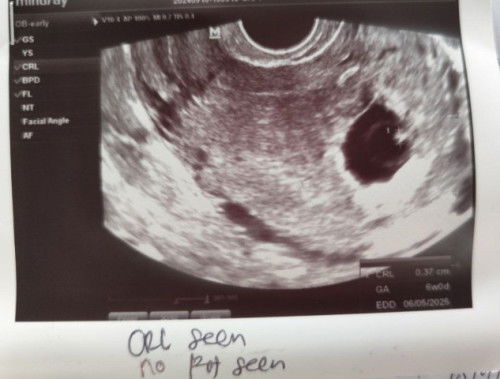

1st scan : ada kantung sahaja. 6w. 2nd scan : 2 minggu selepas 1st scan. Masih 6w. Scan dari bawah : nampak janin (gambar kat bawah). Btw, ada spotting brownish. Sehari sahaja keluar (gambar kat bawah). Doktor bagi masa 2 minggu sebelum next appointment. Ibu² yang ada pengalaman, boleh kongsikan tak?